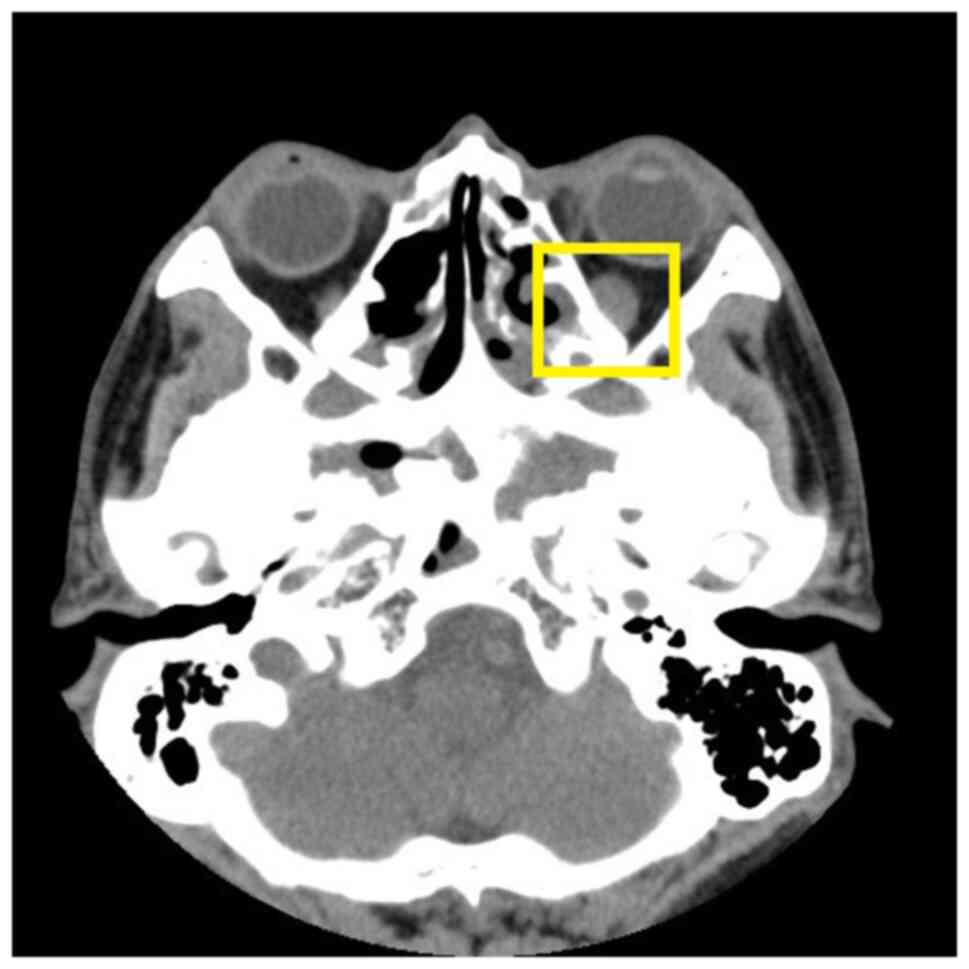

Laboratory investigation revealed the following: All enzymes representing liver and bile duct damage were elevated, including alanine aminotransferase (ALT) at 160 U/l (normal range, 9-50 U/l), aspartate aminotransferase (AST) at 142 U/l (normal range, 15-40 U/l), γ-glutamyl transpeptidase (GGT) at 742 U/l (normal range, 10-60 U/l) and alkaline phosphatase (ALP) at 467 U/l (normal range, 45-125 U/l). Direct bilirubin was slightly elevated to 8.3 µmol/l (normal range, 0-6.8 µmol/l), while albumin was severely reduced to 21.2 g/l (normal range, 40-55 g/l). Both amylase (AMY) and lipase (LPS) were increased to 120 U/l (normal range, 28-100 U/l) and 136.1 U/l (normal range, 13-60 U/l), respectively. The erythrocyte sedimentation rate and procalcitonin were also increased. The T cell spot test was positive. Except for elevated thyroid stimulating hormone (TSH) and anti-thyroglobulin antibody, there were no thyroid function abnormalities [free thyroid (FT) hormone 3, FT4 and anti-thyroid peroxidase antibody were all normal]. Both IgG and IgG4 were elevated to 85.44 g/l (normal range, 7-17 g/l) and 36.9 g/l (normal range, 0.03-2.01 g/l), respectively. Antinuclear antibody was positive. The antigen spectrum of autoimmune liver disease (e.g., anti-mitochondrial antibody-M2), anti-hepatorenal microsomes-1, anti-hepatocyte cytoplasmic antigen type 1 antibody, anti-soluble liver antigen/hepatopancreas antigen antibody, Ro-52, anti-promyelocytic leukemia protein antibody, nuclear autoantigen Sp-100, nuclear pore protein gp210 and 2-ketoacid dehydrogenase complex was negative. Other markers, such as C-reactive protein, complement, immunofixation electrophoresis, coagulation, hepatitis, viral antibody and tumor markers, were normal. The right intraocular pressure was 14 mmHg and the left intraocular pressure was 16 mmHg. The visual acuity of both eyes was 0.6. Defects in the right lower half, right upper half and left infratemporal region were detected in the 30-degree visual field. The synoptic muscle exhibited left inferior oblique paralysis. Orbital CT (Fig. 1) revealed a slightly thickened left inferior rectus muscle and paranasal sinusitis. Mild interstitial changes, slight chronic inflammation in both lungs, small nodules in both lungs, and mediastinal and bilateral axillary lymphadenopathy were detected on pulmonary CT. Prostate hypertrophy and calcification and lymphadenopathy around the bilateral internal iliac vessels were also observed on abdomen-enhanced CT. An ultrasound scan of the superficial lymph nodes revealed that the bilateral neck, bilateral supraclavicular fossa, bilateral subclavian fossa, submental, left axilla, right groin (grades 3-4, suspected malignancy) (Fig. 2), right axilla and left groin (grade 3) exhibited multiple enlarged lymph nodes. A hypoechoic mass was detected in the left submandibular gland. Rough echo of the liver parenchyma and increased elasticity of the liver (10.6 kpa) were observed in the abdominal ultrasound scan.

Figure 1

A thickened left inferior rectus muscle prior to treatment was observed on orbital CT (highlighted area).

The lymph nodes of the bilateral neck, bilateral supraclavicular fossa and submandibular gland became smaller on the ultrasound scan. The lymph node grade at the first two sites changed to grade 2, excluding malignancy. Orbital CT revealed that the enlarged left inferior rectus muscle became slightly narrowed (Fig. 6). The visual acuity of both eyes exhibited marked improvements and the vision of both eyes increased to 1.0.

Figure 6

Slight narrowing of the enlarged left inferior rectus muscle after three months of treatment was observed on orbital CT (highlighted area).